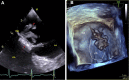

Cardiac Myxoma in a Patient With Hypertrophic Cardiomyopathy

We report a rare case of concomitant hypertrophic cardiomyopathy and cardiac myxoma without LEOPARD syndrome. Additionally, 6 similar cases were systemically reviewed, and the characteristics of this first-ever studied patient group were summarized. (Level of Difficulty: Beginner.).